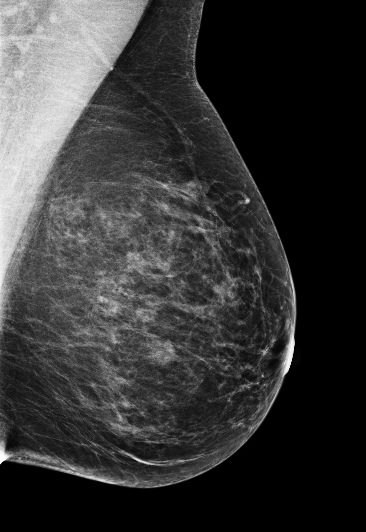

Masking refers to the phenomenon in which a tumor is hidden by the surrounding breast tissue, causing the cancer to be difficult or even impossible to discern with regular mammography, as seen in Figure 2. Masking can also result in large invasive cancers111We define large invasive cancers as those confirmed to have spread and be 2cm at time of diagnosis. – a small cancer may be difficult to discern in certain images, allowing it to grow to a more lethal size. Masking is correlated with breast density, as it has been shown that cancer in dense breasts is more likely to be missed during screening [5, 6, 7]. Density can be subjectively assessed by radiologists via the BI-RADS density standard (ACR) [8, 9], or measured by automated tools such as Libra [10]. These density measurements, however, do not perfectly correlate with masking potential. Radiologists consider the distribution and pattern of tissue when assessing masking potential, and have called for automated methods to assess the masking effect [11]. Until now, the question of exactly how masking potential should be quantified remains an open one, although some subjective notion has been added to certain categories of the most recent edition of BI-RADS density [12].

In this work, we introduce the CSAW-M dataset – a collection of over 10,000 mammographic images and associated masking assessments from experts. The assessments were graded by radiologists according to 8 levels of masking potential, as depicted in Figure 1, from easily assessed mammograms with low-masking potential (level 1) to difficult-to-assess examples with high-masking potential (level 8). This data can be used to train models capable of predicting masking potential from mammographic images in an ordinal classification setting.

The goal of the annotation procedure was to label each image with expert assessments of masking potential. Masking was quantized into 8 bins, or levels, as depicted in Figure 1, for the public training and test sets. Images in the private test set are fully sorted according to masking. Individually sorted examples provide a more granular assessment, but at the cost of increased annotation time. We opted for fine granularity on the private test set because (1) it allows for a more fine-grained assessment, and (2) it allowed us to identify robust initial bins555We use “bin” and “level” interchangeably to denote collections of images with similar masking potential. for the 8 masking levels in the public training/test sets. To represent the initial bins, we chose images personalized to each radiologist, but with highest agreement among the other experts. The benefit to this approach is that the starting point respects subjective assessments while at the same time choosing representative examples for each masking level.

We begin by considering the question how well do the experts agree w.r.t. masking potential? This is an important question to consider, as the main task is to emulate the median expert assessment. Table 3 shows experts have an AMAE ranging from 0.68 to 1.04. This suggests that, on average, individual experts are almost masking levels distant from the ground truth – a reasonable level of agreement. A more nuanced picture of expert agreement is given in Figure 5. Here, agreement between each expert, as well as the ground truth, is measured by Kendall’s . As a rule-of-thumb Kendall’s 0.3 indicates a strong association 666We refer the reader here for an interpretation of Kendall’s .. According to this rule, all experts have a strong association, although we can see that experts 1, 2, and 5 exhibit substantially higher agreement than experts 3 and 4. Interestingly, the experts who tended to agree more were also less experienced. Turning to the F1-scores in Table 3, it is clear that experts are in better agreement for low-masking cases than for high-masking cases. This suggests that high-masking potential is a generally less agreeable property than low-masking potential. Our findings on the public test set are mirrored in the private test set, provided in Appendix F. Examples of mammograms where experts agree and disagree are provided in Figure 4.

The models seem to be more correlated with Experts 1, 2, and 5, who agreed with each other more often (and the ground truth). Interestingly, our models were more correlated with each individual radiologist than any of their colleagues were (see the two rightmost columns in Figure 5). Please note that the cross-tabulation in Figure 5b is asymmetric because the number of mammograms placed into each masking level is different for each radiologist – i.e. the AMAE between two experts changes depending on which one is considered as the reference. In Figure 4, we provide several examples where the networks both agree and disagree with the experts. Figure 4(g) is an interesting case because the density is fairly low but experts rate it as high masking potential. Our models under-estimate the masking, suggesting they rely too heavily on general density cues.